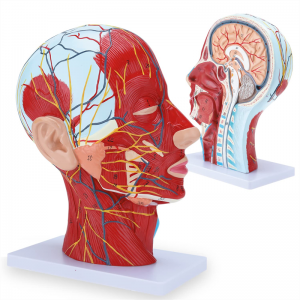

| Izici | Imodeli ikhombisa i-morphology yendawo yezinhlangothi zangaphakathi nezingaphandle zengxenye ye-Median Sagittal yekhanda nentamo, kanye nezinhlaka zemithambo yegazi nezinzwa, futhi kunezingxenye ezingama-84 ezibonisa izibonakaliso zizonke. |

Izici 【Izici】 Kubonisa izicubu ezingezinhle zobuso obudaluliwe; Imithambo yegazi engekho emthethweni nezinzwa zobuso ne-scalp; Izakhiwo ezingaphakathi ze-Parotid Gland & Upper Respiratory Tract; isakhiwo sesigaba se-sagittal somgogodla wesibeletho.

Le modeli ikhombisa imininingwane yekhanda leNhloko yeNhloko yeNhloko ne-Mid sagittal yomuntu. kufaka phakathi okuphezulu

izicubu zobuso obudaluliwe; Imithambo yegazi engekho emthethweni nezinzwa zobuso nesikhumba; Izakhiwo ezingaphakathi

ye-parotid gland nepheshana lokuphefumula elingaphezulu; isakhiwo sesigaba se-sagittal somgogodla wesibeletho.

Le modeli ikhombise i-morphology yendawo yezingxenye zekhanda nentamo yekhanda nentamo kanye nezinhlaka zayo ze-vascular nezinzwa, ezinazo ingqikithi yezinkomba eziyi-100.

Le modeli iyinhloko enkulu yemvelo nemodeli ye-neurovascular yemisipha eyindilinga, isakhi esingu-1, ekhombisa imininingwane yekhanda lelungelo lomuntu kanye nentamo kanye nengxenye ye-Median Sagittal, okubandakanya imisipha engemihle yobuso, imithambo ephakeme yobuso obukhulu bobuso kanye nesikhumba, izinzwa nokwakheka kwempilo kwe-parotid gland kanye nepheshana lokuphefumula elingaphezulu, kanye nesakhiwo seSigaba se-sagittal somgogodla wesibeletho